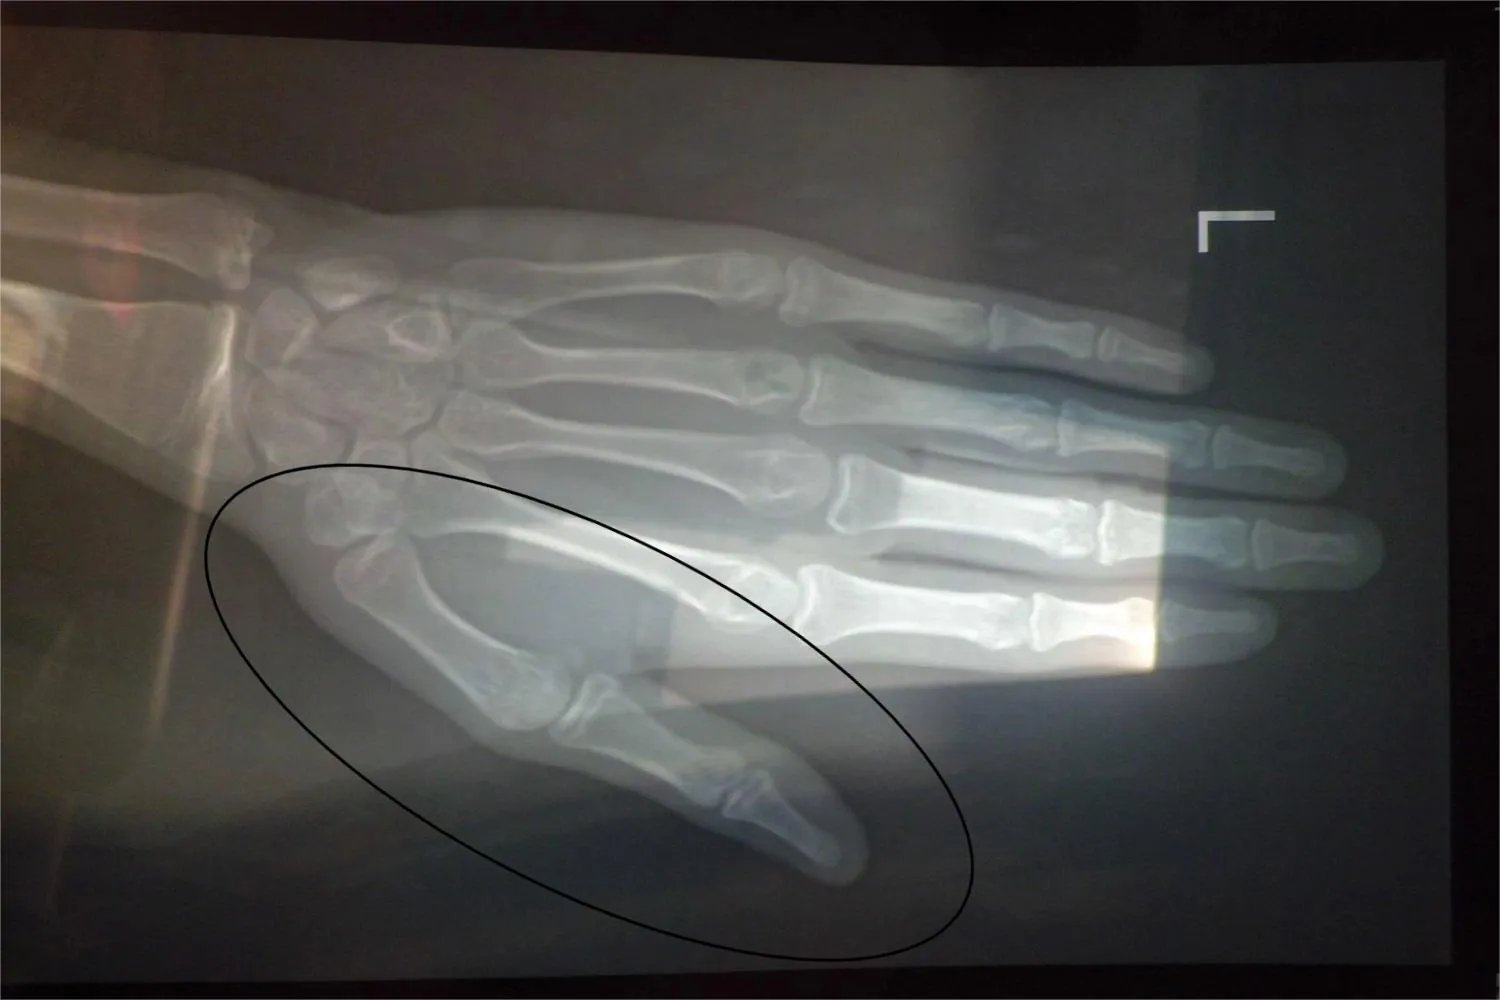

的有关信息介绍如下:概述大拇指的骨头称为指骨,大拇指仅有两节指骨,分别为近端指骨和远端指骨。大拇指的近端指骨、远端指骨及指间关节使其具备了正常的生理功能,能够完成屈伸运动。结构手部有14个指骨,每个指骨都可分为近节指骨、中节指骨、远节指骨,大拇指只有近节指骨和远节指骨。指骨也是小型长骨,指骨的近侧端为底,中部为体,远侧端为滑车。指间关节由各指相邻两节指骨的底和滑车构成,拇指仅有两节指骨,所以只有一个指间关节。

生理意义大拇指掌指关节属于滑车关节,主要作屈伸运动,微屈时,也可作轻微的侧方运动,但运动幅度均较小。从功能上来说,大拇指的功能要占全手功能的一半以上,各种精巧复杂的动作,都需要大拇指的配合,没有大拇指,手的掐、握、抓、捻本领都会大大削弱。指间关节是典型的滑车关节,关节面近似球窝状关节,关节囊松弛,没有回旋活动的肌,加之受两侧韧带的限制,故不能做回旋运动,只能做屈伸、内收外展和环转运动。另外,指间关节仅有一个自由度,有相似于掌指关节的掌板机制和关节囊的限制,所以较坚实,并且带有附加的控制韧带在屈指腱鞘的两侧跨越关节掌侧面,能防止指关节的过伸。